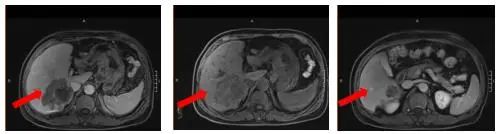

2022-03-01肝脏增强MRI(特异性对比剂):肝内多发转移瘤,大者位于肝右后叶,大小4.6*3.1cm,腹腔内仍见多发肿大淋巴结,直径1.6cm。

图6.治疗5周期后腹部增强MRI